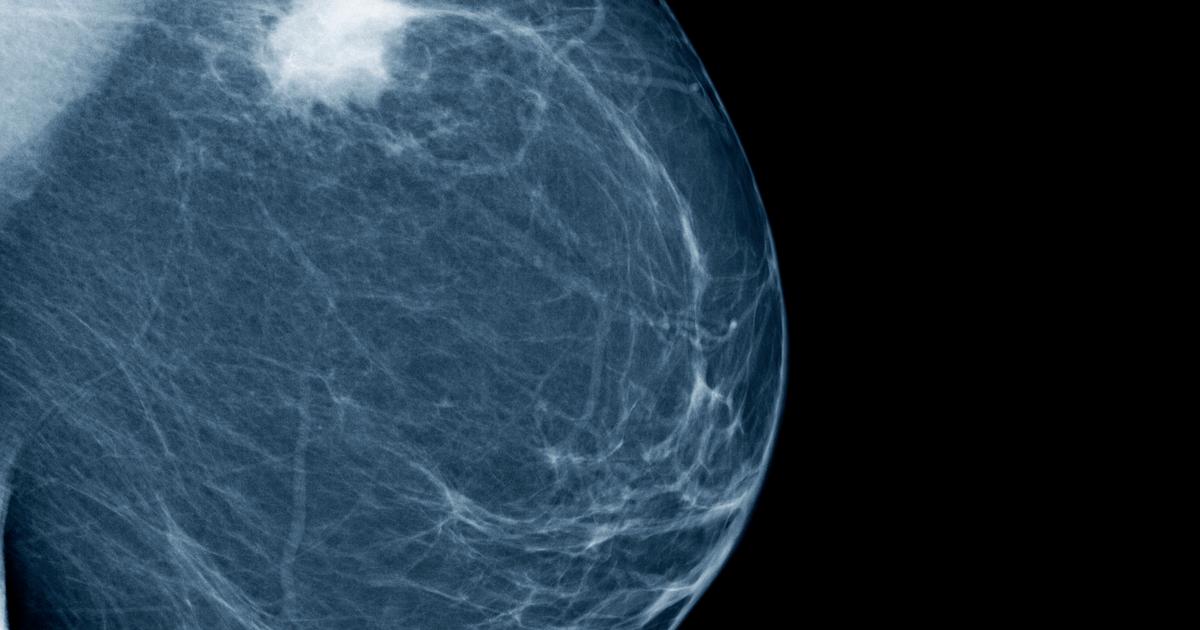

Женщины и дети. Маммография или рентгенографическое исследование молочных желез — диагностическое исследование, которое помогает вывить патологические изменения железистой ткани, опухоль. Маммография проводится при различных изменениях молочных желез. Показания к проведению исследования:. Современные цифровые аппараты позволяют получить высококонтрастные снимки при минимальном облучении пациентки.

Рак молочной железы фото – признаки, виды и стадии, способы лечения. 24 фото с описаниями, представляющие в компактной форме все основные вопросы по раку молочной железы – признаки, симптомы, виды рака, диагностика. Рак молочной железы - фото: Стадии рака молочной железы. 1 стадия рака молочной железы – формируется безболезненный первичный узел, размером до 2 см. Фото галактограммы: а – нормальное ветвление молочных протоков; б – мелкие кисты злокачественную опухоль можно обнаружить на снимке, когда она имеет размеры от 1 до 1,5 см. Рак молочной.